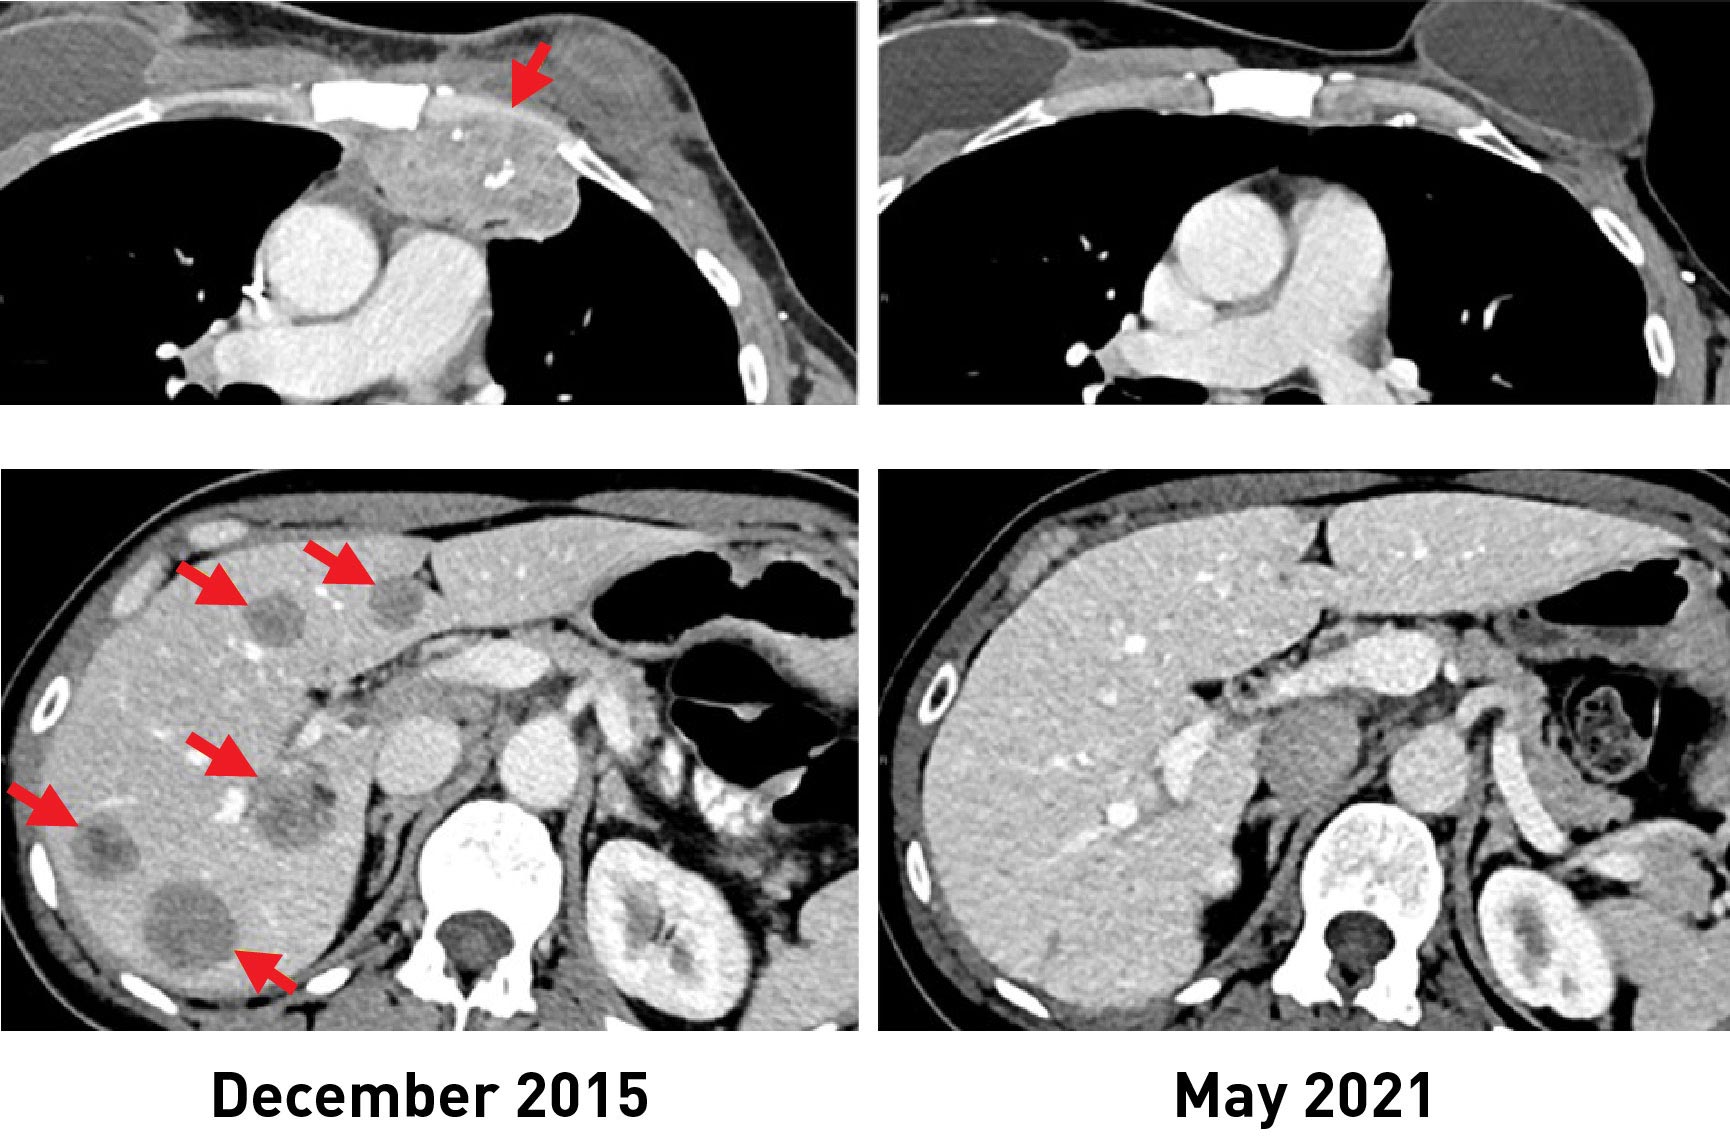

治疗后,这六名妇女中的三人的肿瘤缩小了。其中一位是2018年研究报告中的病例,她至今仍未复发。另外两名妇女在6个月和10个月后,肿瘤分别缩小了52%和69%。然而,一些疾病复发并被手术切除。这些妇女在接受TIL治疗约5年和3.5年后,现在已经找不到罹患癌症的证据。